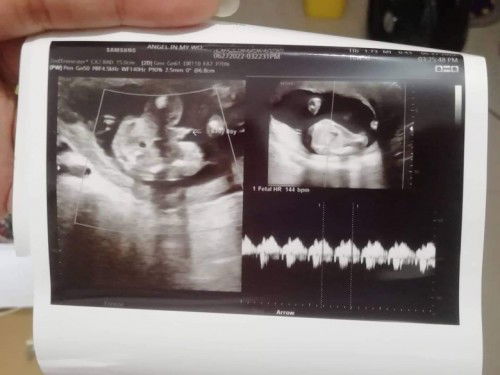

Had my checkup and ultrasound today and we found out the baby's gender this early! It's a boy 🥰